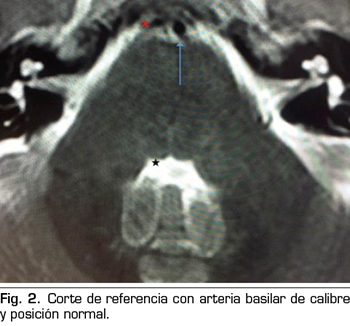

Se hace RM a los 10 días de la aparición de la diplopía objetivando un discreto agrandamiento, elongación y desplazamiento lateral derecho de la arteria basilar, con probable compromiso de espacio en la emergencia de la porción cisternal del VI par derecho (Figuras 1 y 2).

La parálisis del VI PC asociada a CPPD es un diagnóstico por exclusión que requiere la consideración de otras anormalidades neurológicas y oftalmológicas (3). Si la parálisis del VI PC ocurre dentro de las 3 primeras semanas tras la PDA y es precedida de una CPPD, es probablemente consecuencia de la PDA (4). La imagen de la RM puede revelar signos de hipotensión intracraneal, incluyendo engrosamiento meníngeo, colecciones de líquido subdurales y desplazamiento cerebral caudal (11). Estos hallazgos son debidos a la hipotensión intracraneal, sin embargo, no son específicos de la parálisis del VI PC (11). En nuestro caso, la RM no aportaba ninguno de estos signos, pero lo que sí reveló fueron datos de probable compromiso de espacio de una estructura neurológica (emergencia del VI PC derecho) por una estructura vascular (arteria basilar en nuestro caso), planteando el diagnóstico diferencial con un síndrome de compresión neurovascular. El síndrome de compresión neurovascular es definido como el contacto directo con irritación mecánica de los PC por vasos sanguíneos (7). Varios autores han comunicado casos de parálisis unilateral del VI PC, asociada con el contacto neurovascular entre el VI PC y la arteria vertebral o basilar en la RM (6).